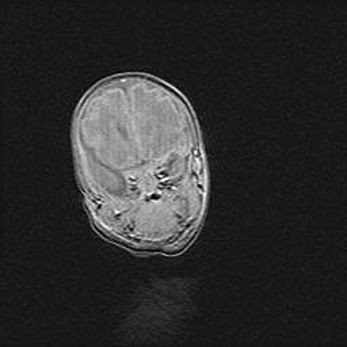

Подострая гематома правой гемисферы мозжечка.

Наружная гидроцефалия.

Возраст: 15 дней

Вес: 3100 г

Пол: женский

Окружность головы: 37 см

Срок гестации: 35-36 недель

При открытой наружной форме гидроцефалии у новорожденных расширяются и переполняются субарахноидные пространства.

Кровоизлияния в мозжечок имеют две клинико-анатомические формы: полушарные гематомы и кровоизлияния в червь.

К появлению этой патологии может привести: повреждения головного мозга, возникающие в результате асфиксии и гипоксии плода при беременности, или травмы во время родов. Редко гематома мозжечка может быть результатом первичной коагулопатии и сосудистой мальформации, диссеминированном внутрисосудистом свертывании, изоиммунной тромбоцитопении.